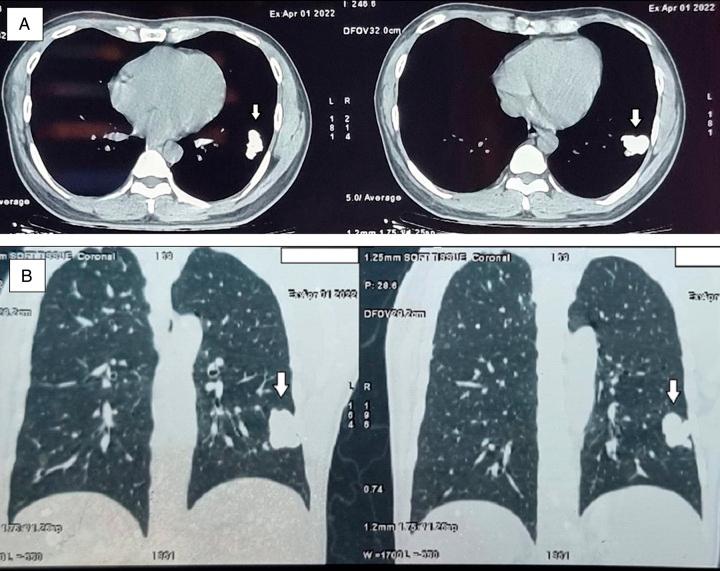

The authors present a clinical case of a 42-year-old patient who was diagnosed with MC 8 years ago, now admitted to the hospital with a palpable epigastric mass. Clinical and laboratory examinations showed consistent results for MC tumours, with metastasis to the body and tail of the pancreas and invasion of the splenic vein. Surgical resection and systemic screening were performed to ensure that there were no lesions elsewhere. Regular follow-up has found no localized lesions or complications after 15 months.

作者报告了一例临床病例,一名42岁患者8年前被诊断为MC,现因上腹部可触及肿块入院。临床和实验室检查结果与MC肿瘤相符,已转移至胰腺体尾部并侵犯脾静脉。进行了手术切除和全身筛查以确保其他部位无病变。定期随访发现15个月后无局部病变或并发症。

胰腺转移性骨骼外间叶性软骨肉瘤极为罕见。据我们目前了解,医学文献中仅记录了14例此类病例。胰腺转移的症状多样,转移性间叶性软骨肉瘤的影像学特征通常不典型。